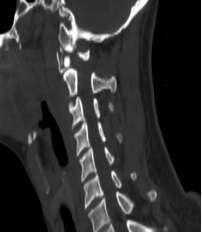

患者杨先生在春节后返苏的高速上不慎发生车祸,事故发生后患者感觉颈部剧烈疼痛,无法活动。当天送至我院后,在急诊拍摄颈椎CT显示:第一颈椎骨折,移位明显。

在仔细研究了患者的片子后,发现寰椎前后弓四处骨折,双侧侧块漂浮,寰齿间隙增大,后弓的骨折块还陷入到椎管内。尽管没有造成颈髓损伤,但稍有移动就可能导致瘫痪甚至死亡,因此姜主任确定该患者的最佳治疗方案为寰枢椎内固定手术。